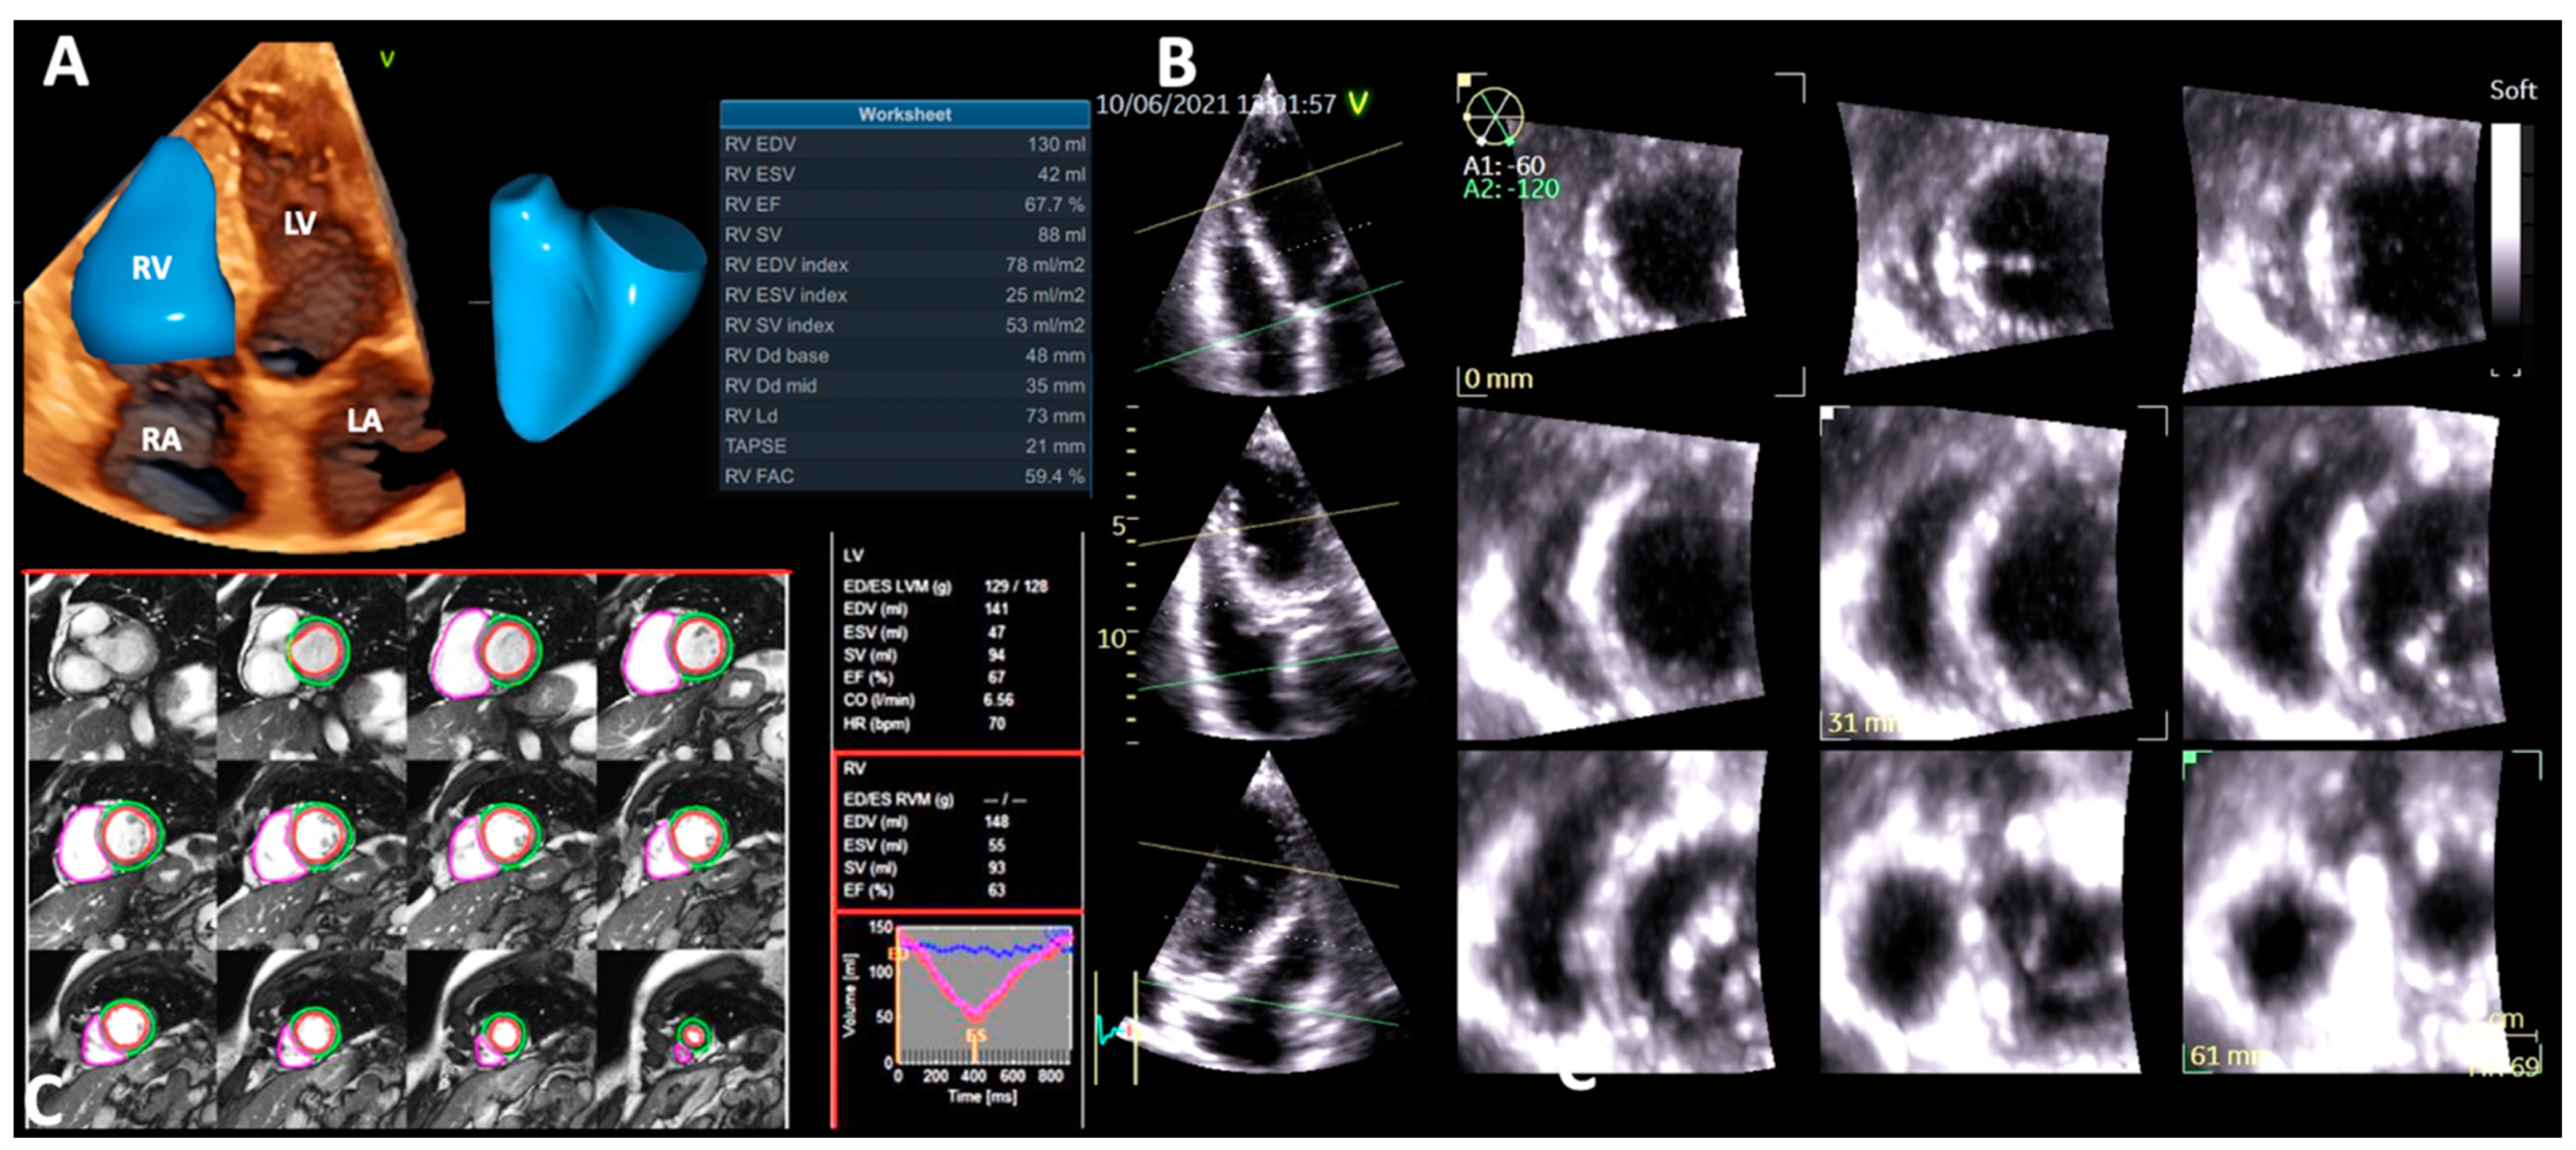

4.1.6. Right Ventricular Ejection Fraction by Three-Dimensional Echocardiography

4.2. Cardiac Magnetic Resonance